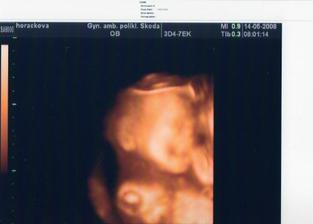

•••••••••• 16.4.2008 (19+5tt) výsledky z tripplů máme v pořádku, dostali jsme první 3D fotečku, jen nám paní doktorka nakonec nedělala screening ve 20tt, protože nám ho budou dělat v pondělí 21.4. v Praze (prý stačí jen jednou)